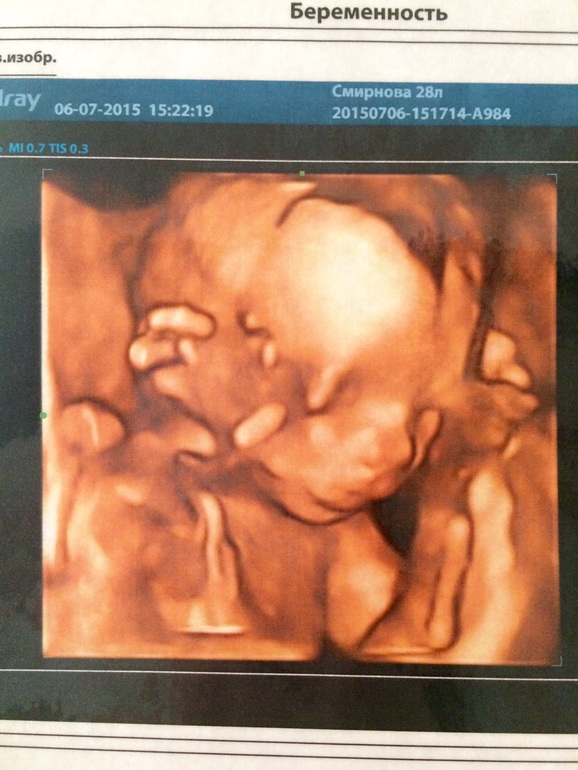

Теперь про сам осмотр , у нас всё хорошо сынок весит 250 гм, срок 18,4 недели Б , чсс 133 уд/мин, а КРТ почемуто не написали(( . Длина шейки 39мм, по допилерометрии тоже всё в норме, а вот в околоплодных водах нашли мелкие и крупные взвесь ( хлопья ) что это я не понимаю, направили сдать анализы на torch инфекции . У меня теперь к вам вопрос у кого было что- то подобное ???

Ну и фото нашего мальчика )))

На втором 18,4 недель .